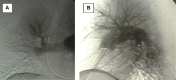

Introduction: Hughes-Stovin syndrome is a life-threatening disorder of unknown etiology. This condition is characterized by vasculitis, deep venous thrombosis and aneurysms that mainly involve the pulmonary arteries resulting in hemoptysis. It has been described in literature less than 40 times. However, we believe it is not very uncommon as it might be diagnosed as pulmonary embolism solely. In such cases, anticoagulation therapy augments the risk of life-threatening hemoptysis.

Materials and methods: We report the case of a 35 years old, Egyptian female patient with Hughes-Stovin syndrome, who initially presented with lower limb deep vein thrombosis and coughing of blood. Anticoagulation regimen for pulmonary embolism was given. This resulted in massive hemoptysis that was successfully controlled by medical therapy.